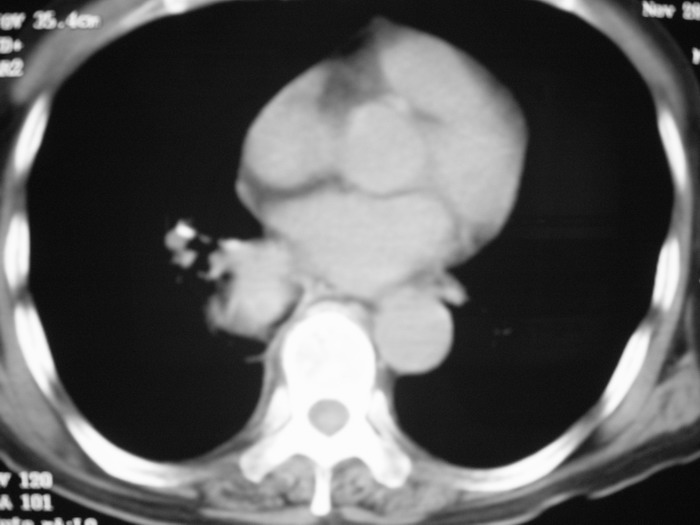

m、70y,反复咳嗽2月。请各位同仁给定位1、(肺?,纵隔?)2、定性。感谢!!

右后纵隔良性占位性病变,神经原性肿瘤可能性大,就其形态看,高密度囊肿待排,建议mri检查。

右下肺纵隔旁较大 均匀密度肿块,部分边缘植入纵隔,气管明显受压 变形。支持:后纵隔肿瘤!首选:神经源性!不支持肺内肿瘤原因:1 肿瘤位于下叶支气管及背段支气管开口区,但未侵犯支气管,只是受压表现。2 纵隔内未见肿大淋巴结。3 肺内未见阻塞性肺炎。

肺上有多个小结节哦,考虑转移,那就应该是恶性的啊